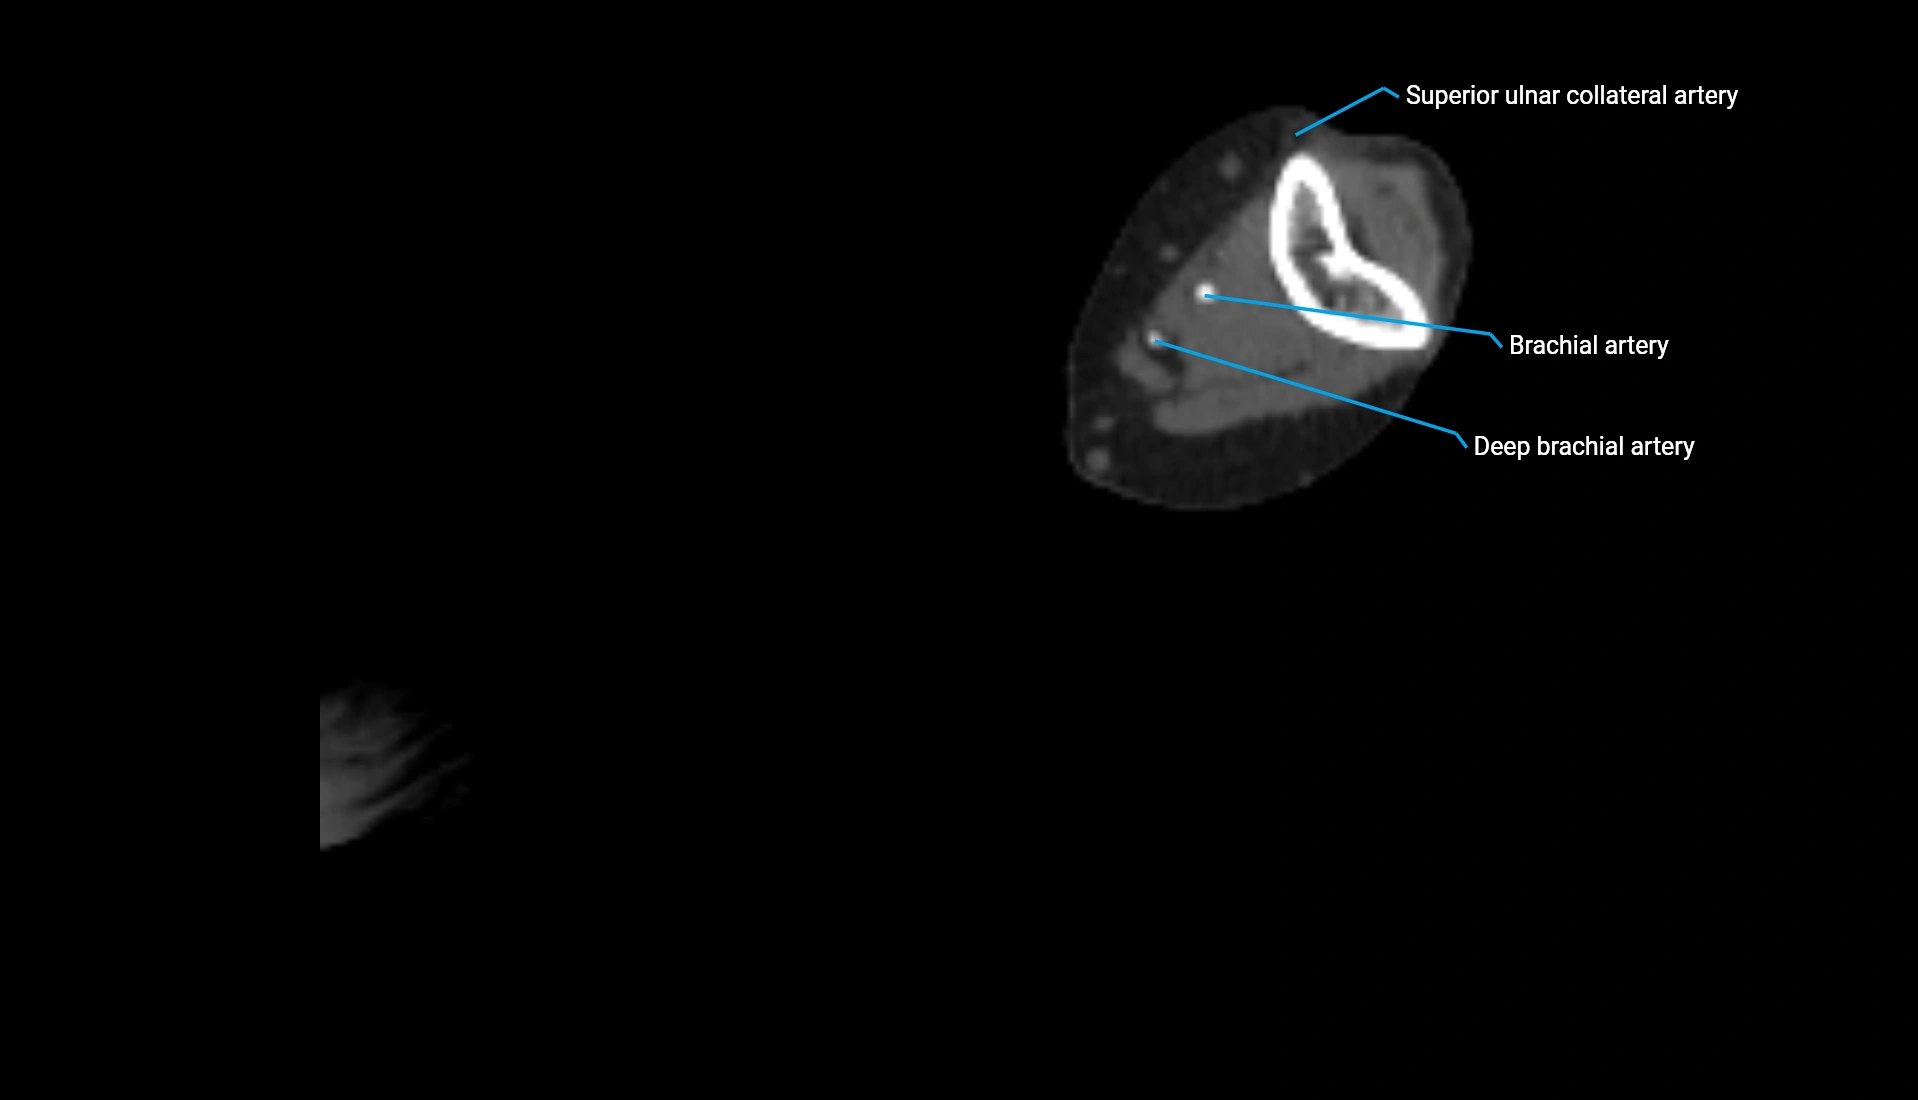

CT Appearance

Non-Contrast CT:

• Cortex: High-density, sharply defined

• Subchondral bone: Dense cancellous matrix

• Articular surface: Smooth concave contour articulating with the capitellum

• Excellent for evaluating bone integrity, alignment, and subtle fractures